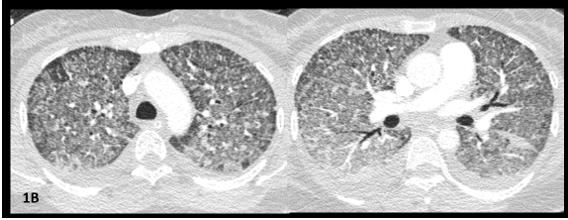

A 46-year-old Indonesian woman living in Portugal since 2018, presented to the emergency department with a 15-day history of fever, non-productive cough, headache, and fatigue. She had no relevant past medical history or exposures and was not on any medication or recreational drugs. She had no known history of contact with COVID-19 patients. Besides fever, physical examination was unremarkable. Initial workup revealed hypoxemic respiratory failure (paO2 55.1mmHg breathing room air) and slightly elevated C-reactive protein (6,91mg/dL). Real time polymerase chain reaction (PCR) for SARS-CoV-2 and HIV-ELISA test were negative. A CT scan showed widespread micronodules with random distribution, suggestive of a miliary pattern (Figure1A).

At day seven, she was transferred to the ICU due to sudden worsening respiratory failure (RF) (tachypnea, PaO2/ FiO2<100mmHg). Empirical piperacillin/tazobactam and azithromycin were added, presuming superimposed hospitalacquired bacterial infection. After an unsuccessful 16-hour trial of high-flow oxygen therapy, she was intubated and mechanically ventilated (Vt 6ml/kg, PEEP 10cmH20). CT angiogram ruled out pulmonary emboli and air-leak syndromes, showing worsened micronodules and new-onset symmetrical ground glass opacities with anteroposterior density gradient and small bilateral pleural effusion (Figure1B).